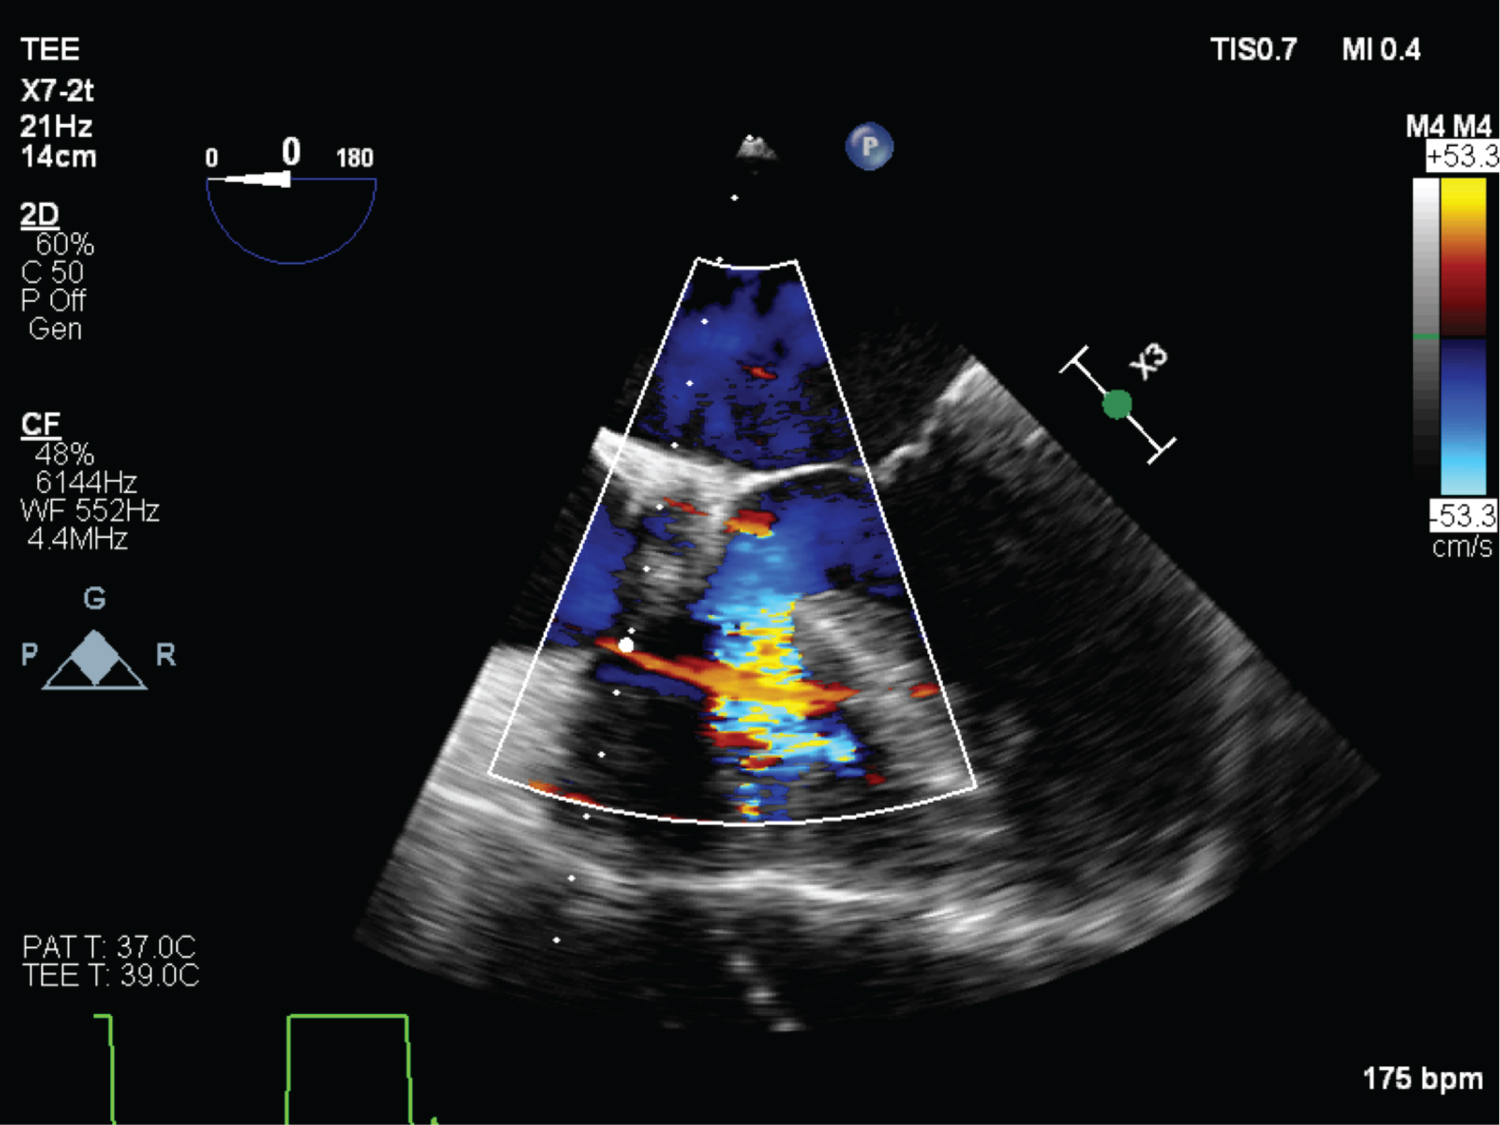

On echocardiography, aneurysmal appearance of the involved sinus and the presence of a “windsock,” protruding into the receiving chamber are characteristic of RSOV [7] (Figure 1, Figure 2, Figure 3, Figure 4 and Figure 5) ( Video 1 and Video 2 ).

Figure 1: (TEE) Mid esophageal RV inflow-outflow view showing RSOV (Wind sock deformity). View Figure 1

Figure 2: (TEE) Mid esophageal RV inflow-outflow view with colour doppler showing RSOV, VSD hypertrophied RV ridge. View Figure 2